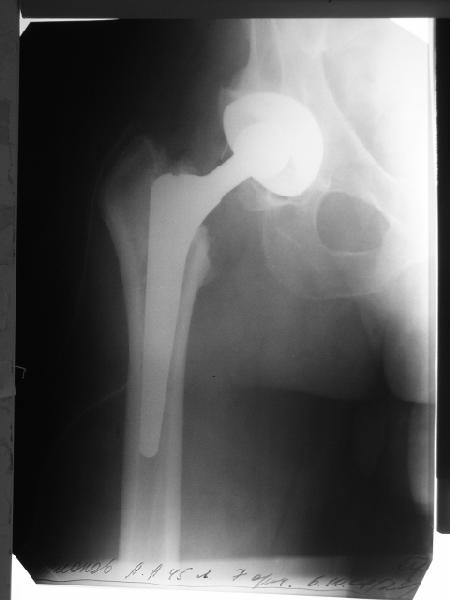

Мужчине 1963 г. бедра в октябре прошлого года в Кургане сделано

эндопротезирование правого тазобедренного сустава (последствия перелом

шейки бедра) бесцементным протезом Cerafit.

Все было благополучно, пациент уже ходил без трости, когда в начале

января 2009 упал на улице на правый бок.

Госпиталирован по месту жительства (МСЧ г. Новоуральск). Уложен на

скелетное вытяжение. На снимках от 3 февраля видно миграцию ножки в

дистальном направлении, она явно нестабильна.